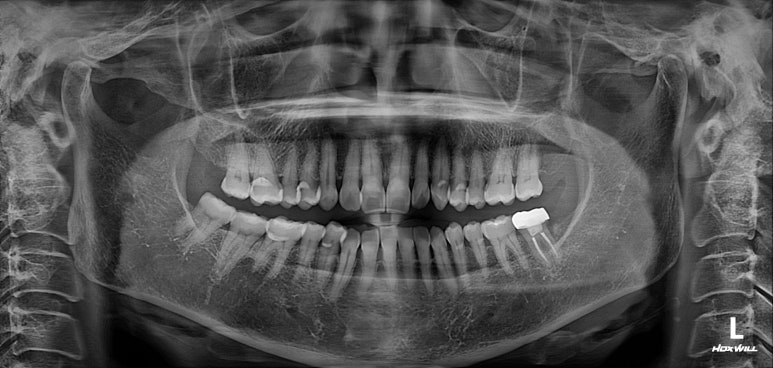

치과용 파노라마 사진을 보았을 때, 전체적으로 건강해보이는 분이었습니다. 건치왕!!!!

치경부 (=치아의 목부분)에 약간의 마모가 되어있는 것이 보이긴 하지만, 충치가 있을 것 같지 않은 분위기..

앞니의 치경부 마모가 눈에 띄긴 하지만, 전체적으로 쌓여있는 치석말고는 별 문제가 없었습니다.

치료 끝나고 7개월 뒤에 내원하셨을 때의 치과용 파노라마 사진입니다.

보시면 지르코니아 크라운으로 깔끔하게 씌워져 있는 것을 보실 수 있을텐데요~ 크랙이 있는 치아가 벌어지는 힘에 저항하려면, 반드시 크라운으로 씌워주어야 합니다.